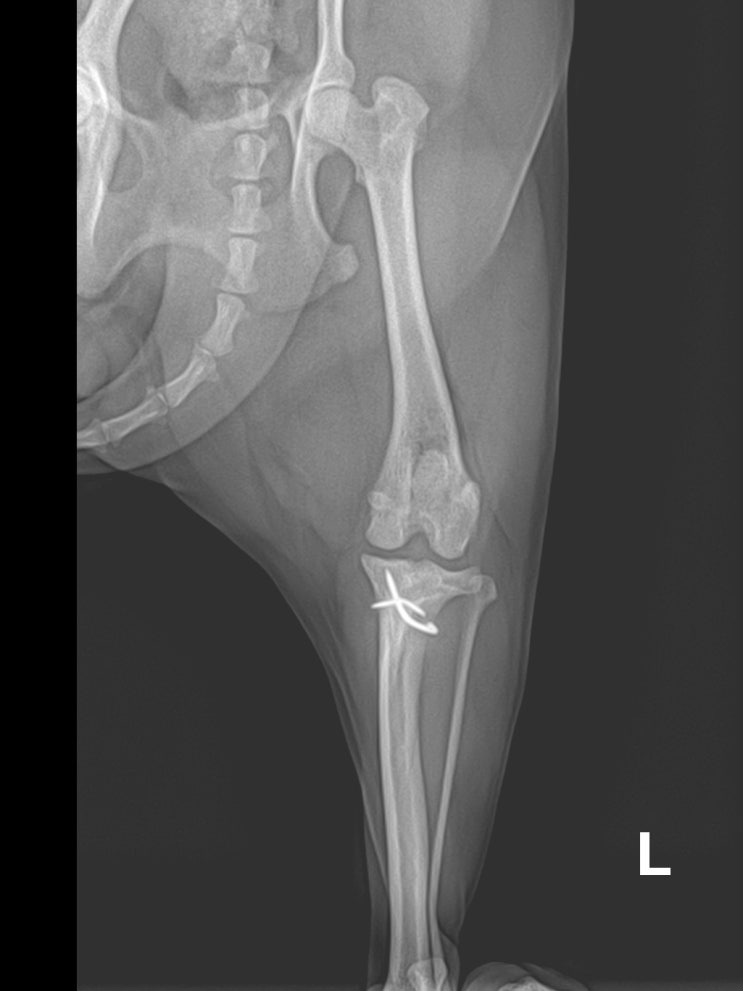

1살 푸들 강아지 슬개골 탈구 수술 후기 / 반려견 슬개골 외측 인대 파열 수술 가격, 비용 / 강아지 뒷다리를 들고 걷는 이유 / 애완견 무릎 수술 전문 24시 동물병원

안녕하세요~ 굿파파 수의사입니다. 내일은 식목일이네요^^* 주말에 가족과 함께 나무 심는 시간을 갖는 건 ...